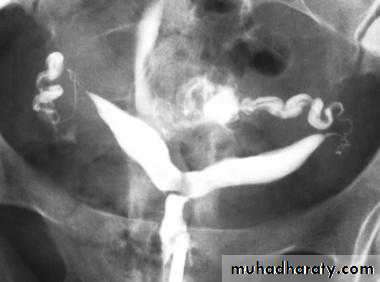

Hysterosalpingography bicornuate uterus

Hysterosalpingography rudimentary horn and clubbing